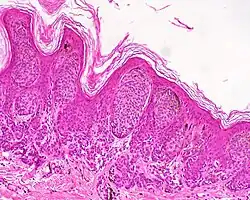

A melanocytic nevus (also known as nevocytic nevus, nevus-cell nevus, and commonly as a mole)[1][2] is a usually noncancerous condition of pigment-producing skin cells. It is a type of melanocytic tumor that contains nevus cells.[2] A mole can be either subdermal (under the skin) or a pigmented growth on the skin, formed mostly of a type of cell known as a melanocyte. The high concentration of the body's pigmenting agent, melanin, is responsible for their dark color. Moles are a member of the family of skin lesions known as nevi (singular "nevus"), occurring commonly in humans.[3][4] Some sources equate the term "mole" with "melanocytic nevus",[2] but there are also sources that equate the term "mole" with any nevus form.[3]

| Junctional nevus | Along the junction of the epidermis and the underlying dermis.[16] | May be colored and slightly raised.[17] |

ICD10: D22 ICDO: M8740/0 |